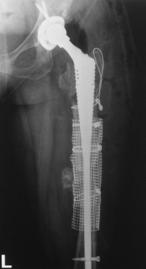

Trei din cele 38 de solduri investigate au prezentat ca indicatie operatorie fractura periprotetica, doua solduri fiind diagnosticate cu fractura Vancouver B3, iar unul cu fractura Vancouver B2. Fracturile Vancouver B3 au fost tratate in ambele cazuri prin extractia protezei si introducerea unei proteze tip DLS de 275 mm lungime impreuna cu solidarizarea ansamlului folosind cate o placa si 4 cabluri in fiecare caz. Fractura Vancouver B2 a fost tratata prin extractia protezei si inlocuirea acesteia cu o proteza tip Modular.